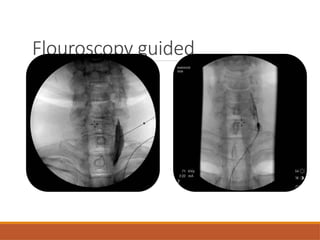

FLOUROSCOPY GUIDED

Landmarks and patient positioning similar to blind technique

Bony delineation better – fluoroscopy

Soft tissues including vascular structures -ultrasound

Both the C6 transverse process approach and the C7 anterior

paratracheal approach can be done

Contrast to confirm appropriate needle placement

◦ Proper facial plane- local spread of contrast between the tissue planes both

cephalad and caudad.

◦ Striated appearance – Intramuscular

◦ Intravascular injection -immediate dissipation of dye